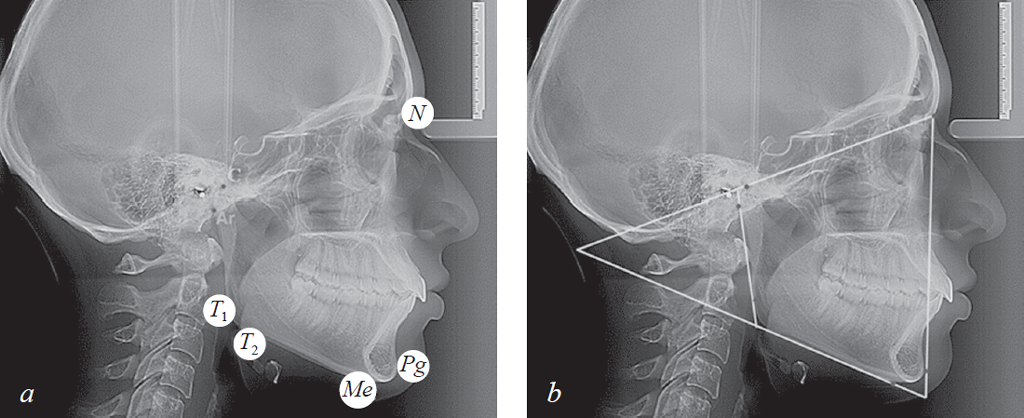

В качестве основных точек использовали точку: N (Nasion), расположенную в месте соединения лобной и носовых костей; C (Condylion), наиболее высокую точку суставной головки; Ar (Articulare) — дистальный контур шейки суставной головки нижней челюсти; T1 — заднюю верхнюю выпуклость угла нижней челюсти; T2 — заднюю нижнюю выпуклость угла нижней челюсти; Ме (Menton) — наиболее низкую точку на контуре нижней челюсти, в месте наложения симфиза; Pg (Pogonion) — переднюю точку подбородочного выступа.

Во-первых, на телерентгенограмму наносили общепринятые точки: N, C, Ar, T1, T2, Pg.

Указанные точки служили ориентиром для проведения реперных линий (плоскостей), которые использовали в качестве ориентиров для сопоставления фрагментов томограмм с телерентгенограммой. В горизонтальном направлении проводили две линии. Верхняя линия, через точки N и С, отделяла лицевой отдел головы от краниального, и нами обозначалась как плоскость лицевого отдела головы или краниофасциальная линия (KFL).

Мандибулярная плоскость (МL) проходила через точки Gn и T2. Пересечение линий МL и KFL образовывало челюстно-лицевой угол, который может быть использован в качестве показателя типа роста лица (горизонтальный, вертикальный и нейтральный).

В вертикальном направлении соединяли точки N и Pg, полученную линию обозначали как «вертикальную линию лица». Касательная линия к ветви нижней челюсти (Ar – T1) с мандибулярной плоскостью образовывала угол нижней челюсти (рис. 1).

Рис. 1. Основные точки (a); линии используемые в качестве основных ориентиров для сопоставления рентгенограмм (b)

Fig. 1. Main points (a); lines used as the main reference points for the comparison of radiographs (b)